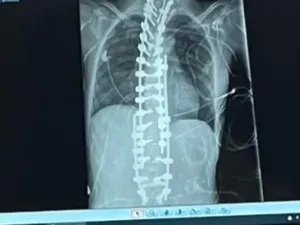

Seorang pria yang tidak disebutkan identitasnya tidak sadar mengidap penyakit langka dan menjadi donor sperma. Akibatnya, 10 anak didiagnosis kanker.